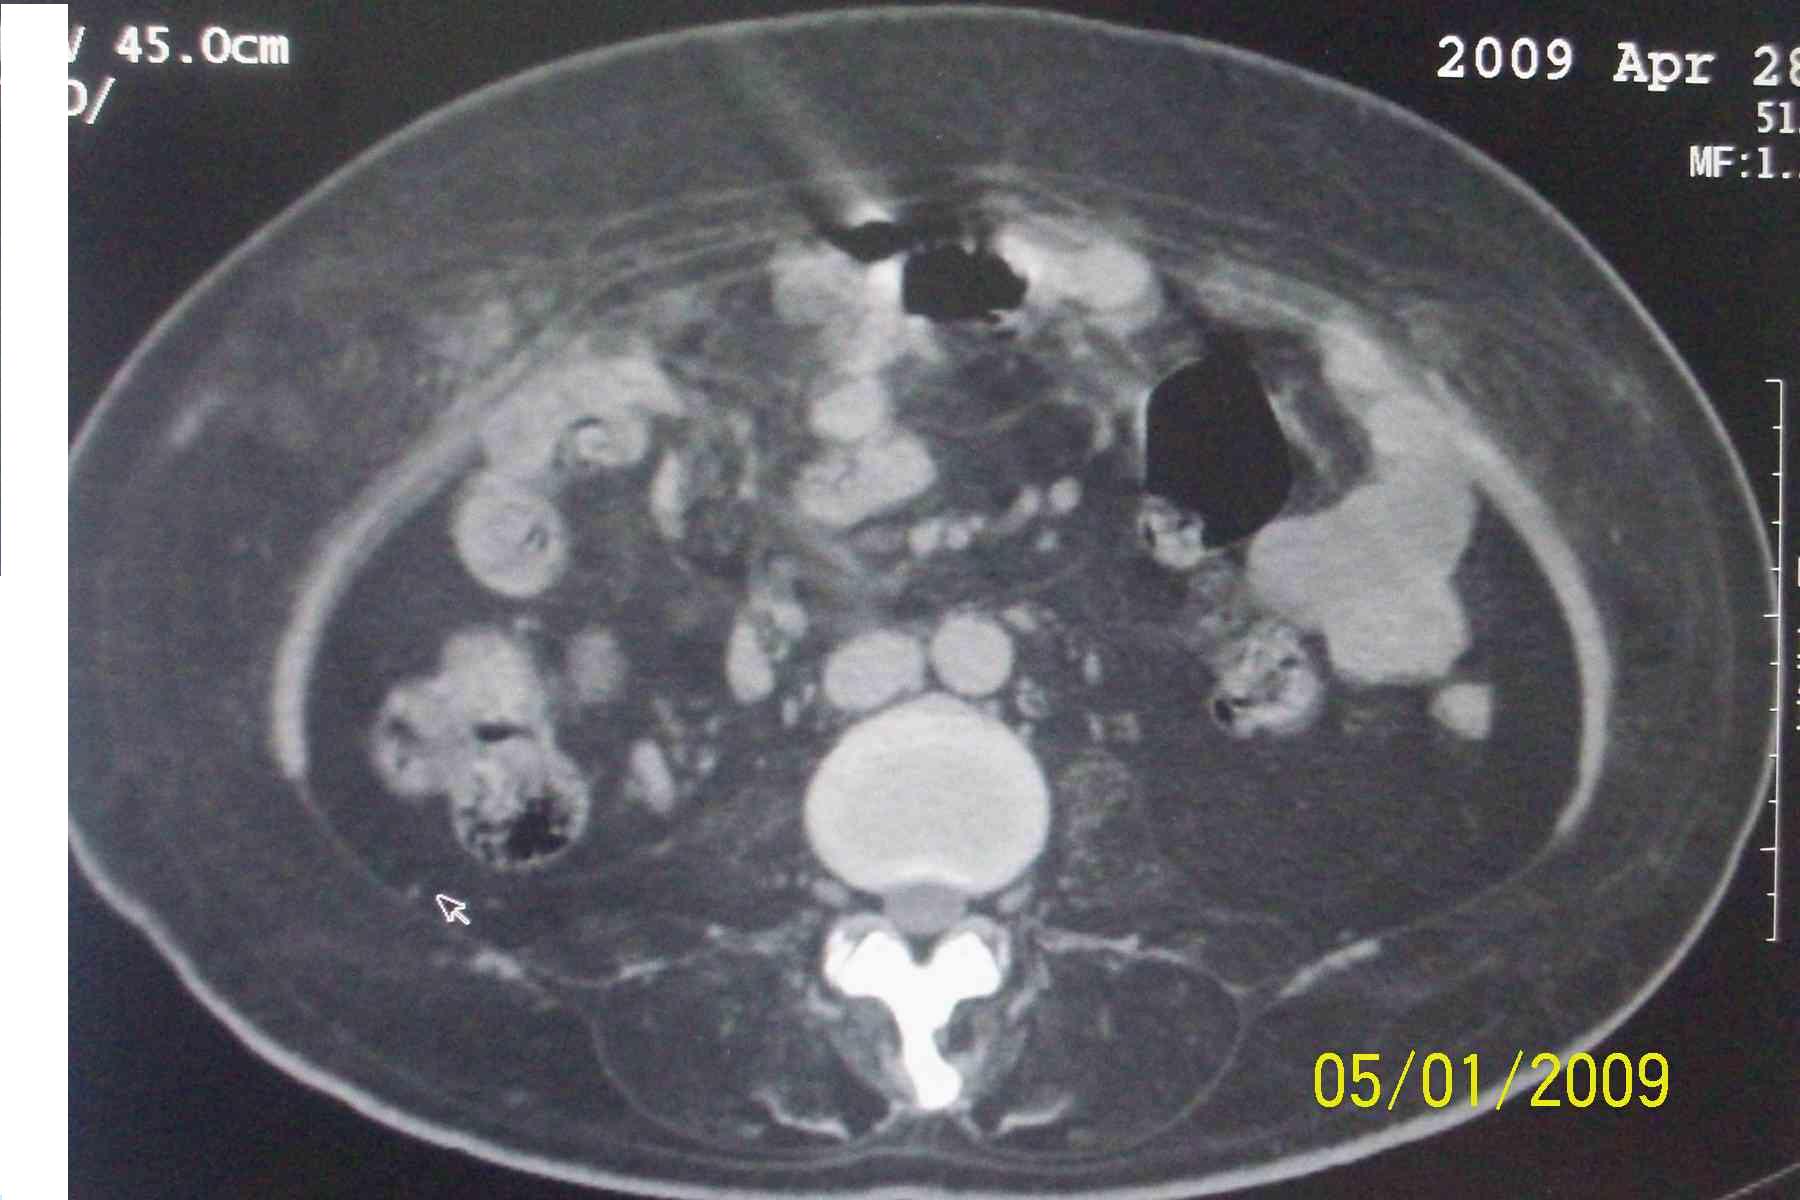

以下是引用杀毒软件在2009-5-1 17:43:00的发言:[br]良性对称性脂肪增多症

以下是引用ncy888888在2009-5-1 17:39:00的发言:[br]肾怎么弄丢了一个。